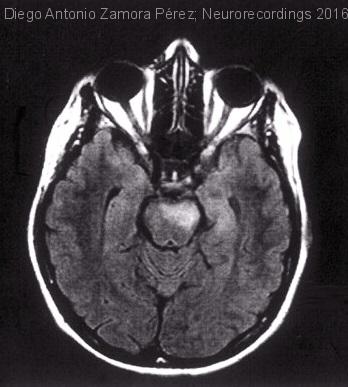

Cefalea y hemiparesia subagudos en paciente con aftas orales y uveítis de repetición

Hombre | 32 años

Diagnóstico final: Síndrome de neuro-Behçet

Varón de 32 años de edad con antecedente personal de enfermedad de Behçet en control por servicio de Reumatología. El paciente es ingresado por un cuadro de varias semanas de evolución consistente en episodios de...